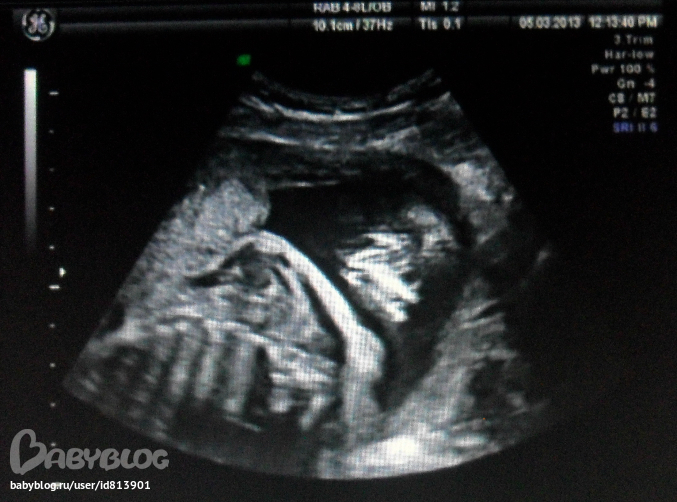

Это наш затылок со спинкой и плечиками, если кто разберёт то узист нам показывал какие мы уже волосатики (белые рваные линии сверху плечевой дуги - волосики)

Тут наш профиль, потом носогубный треугольник, личико в 3Д и последняя фотка того как наша зайка зевает сладко)))))